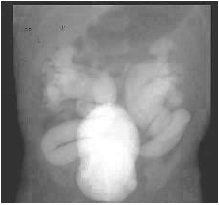

Uma criança de 2 anos de idade com diagnóstico de mielodisplasia, bexiga neurogênica e esvaziamento vesical através de cateterismo intermitente vem apresentando infecções urinárias de repetição e pielonefrite com necessidade de internação. Faz uso de oxibutinina oral em dose máxima três vezes ao dia e bactrim profilático. A ultrassonografia mostrou ureteroidronefrose bilateral. Com base na uretrocistografia abaixo, a conduta indicada para o caso é: